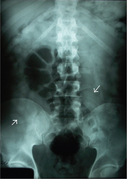

Large bowel obstruction (Cecal volvulus; black arrows).

Gallstones (not sensitive)